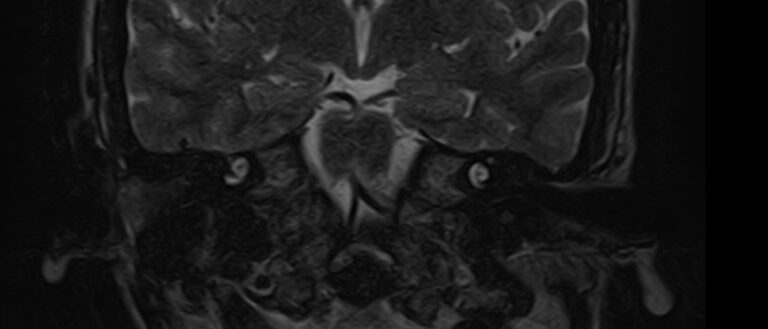

Внутреннее ухо – важная часть слуховой и вестибулярной систем тела человека, находящаяся в толще пирамиды височной кости.

Внутреннее ухо содержит слуховой орган (улитку) и орган равновесия (преддверие и полукружные каналы), патологические изменения которых в свою очередь приводят к развитию нейросенсорной тугоухости и вестибулярных нарушений.

МРТ внутреннего уха применяется при:

• нейросенсорной и смешанной тугоухости;

• заложенности и шуме в ушах;

• приступах головокружения, неустойчивости при ходьбе;

• подозрении на образование преддверно-улиткового нерва;

• планировании хирургических вмешательств (кохлеарной имплантации) для оценки анатомических особенностей внутреннего уха.